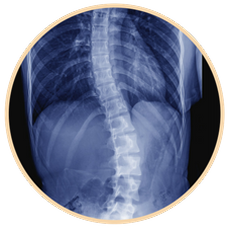

Scoliosis